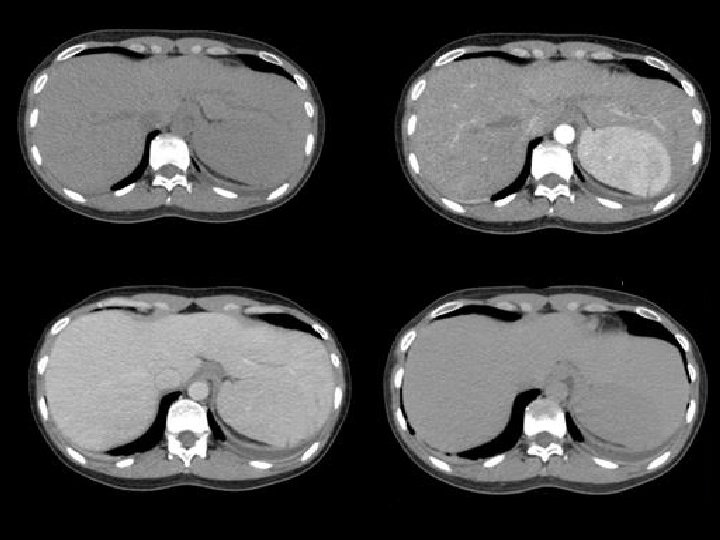

Protocolo de estudio • Sin contraste • Fase precoz • Fase v-p • Tardía

Protocolo de estudio • Sin contraste • Fase precoz • Fase v-p • Tardía 5 minutos

Protocolo de estudio • Sin contraste • Fase precoz • Fase v-p • Tardía 5 minutos SI O SI PARA VER BAZO